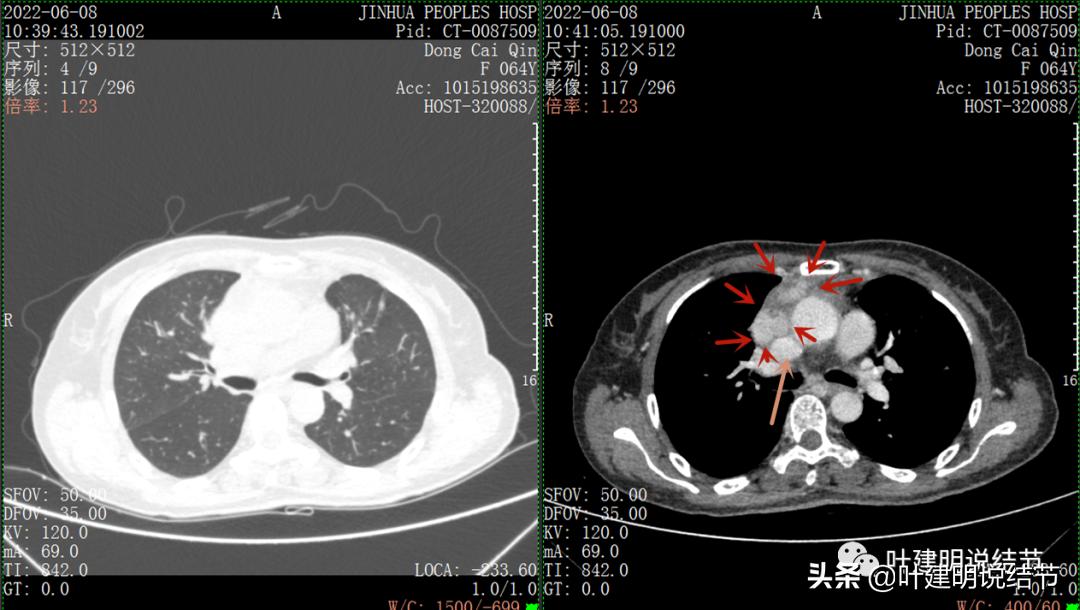

以下图片左侧是肺窗,右侧是纵隔窗。红色箭头示病灶,桔色箭头示无名静脉,黄色箭头示支气管,砖色箭头示上腔静脉,蓝色箭头示主动脉,紫色箭头示肺动脉。

病灶纵隔胸膜侧非常光滑,说明来源于纵隔

粉色箭头示淋巴结可能